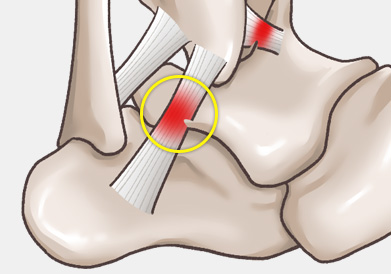

발목 인대 파열은 발목 관절을 지지하는 인대가 외부 충격이나 과도한 움직임으로 인해 늘어나거나 찢어지는 손상을 말합니다.

발목을 접질리거나 회전 손상을 입는 경우 발생할 수 있으며, 스포츠 활동 중, 낙상, 교통사고 등 다양한 원인으로 발생할 수 있습니다.

주로 다음 그림처럼 내반(inversion)에 의해 바깥쪽 인대가 파열되는 경우가 흔하며, 그 중에서도 전거비인대 및 종비인대의 손상 여부가 수술을 결정하는 데 가장 중요합니다.

3도 손상의 경우 전거비인대 완전 파열 뿐만 아니라 종비인대의 손상도 흔히 같이 동반되어 있기 때문에